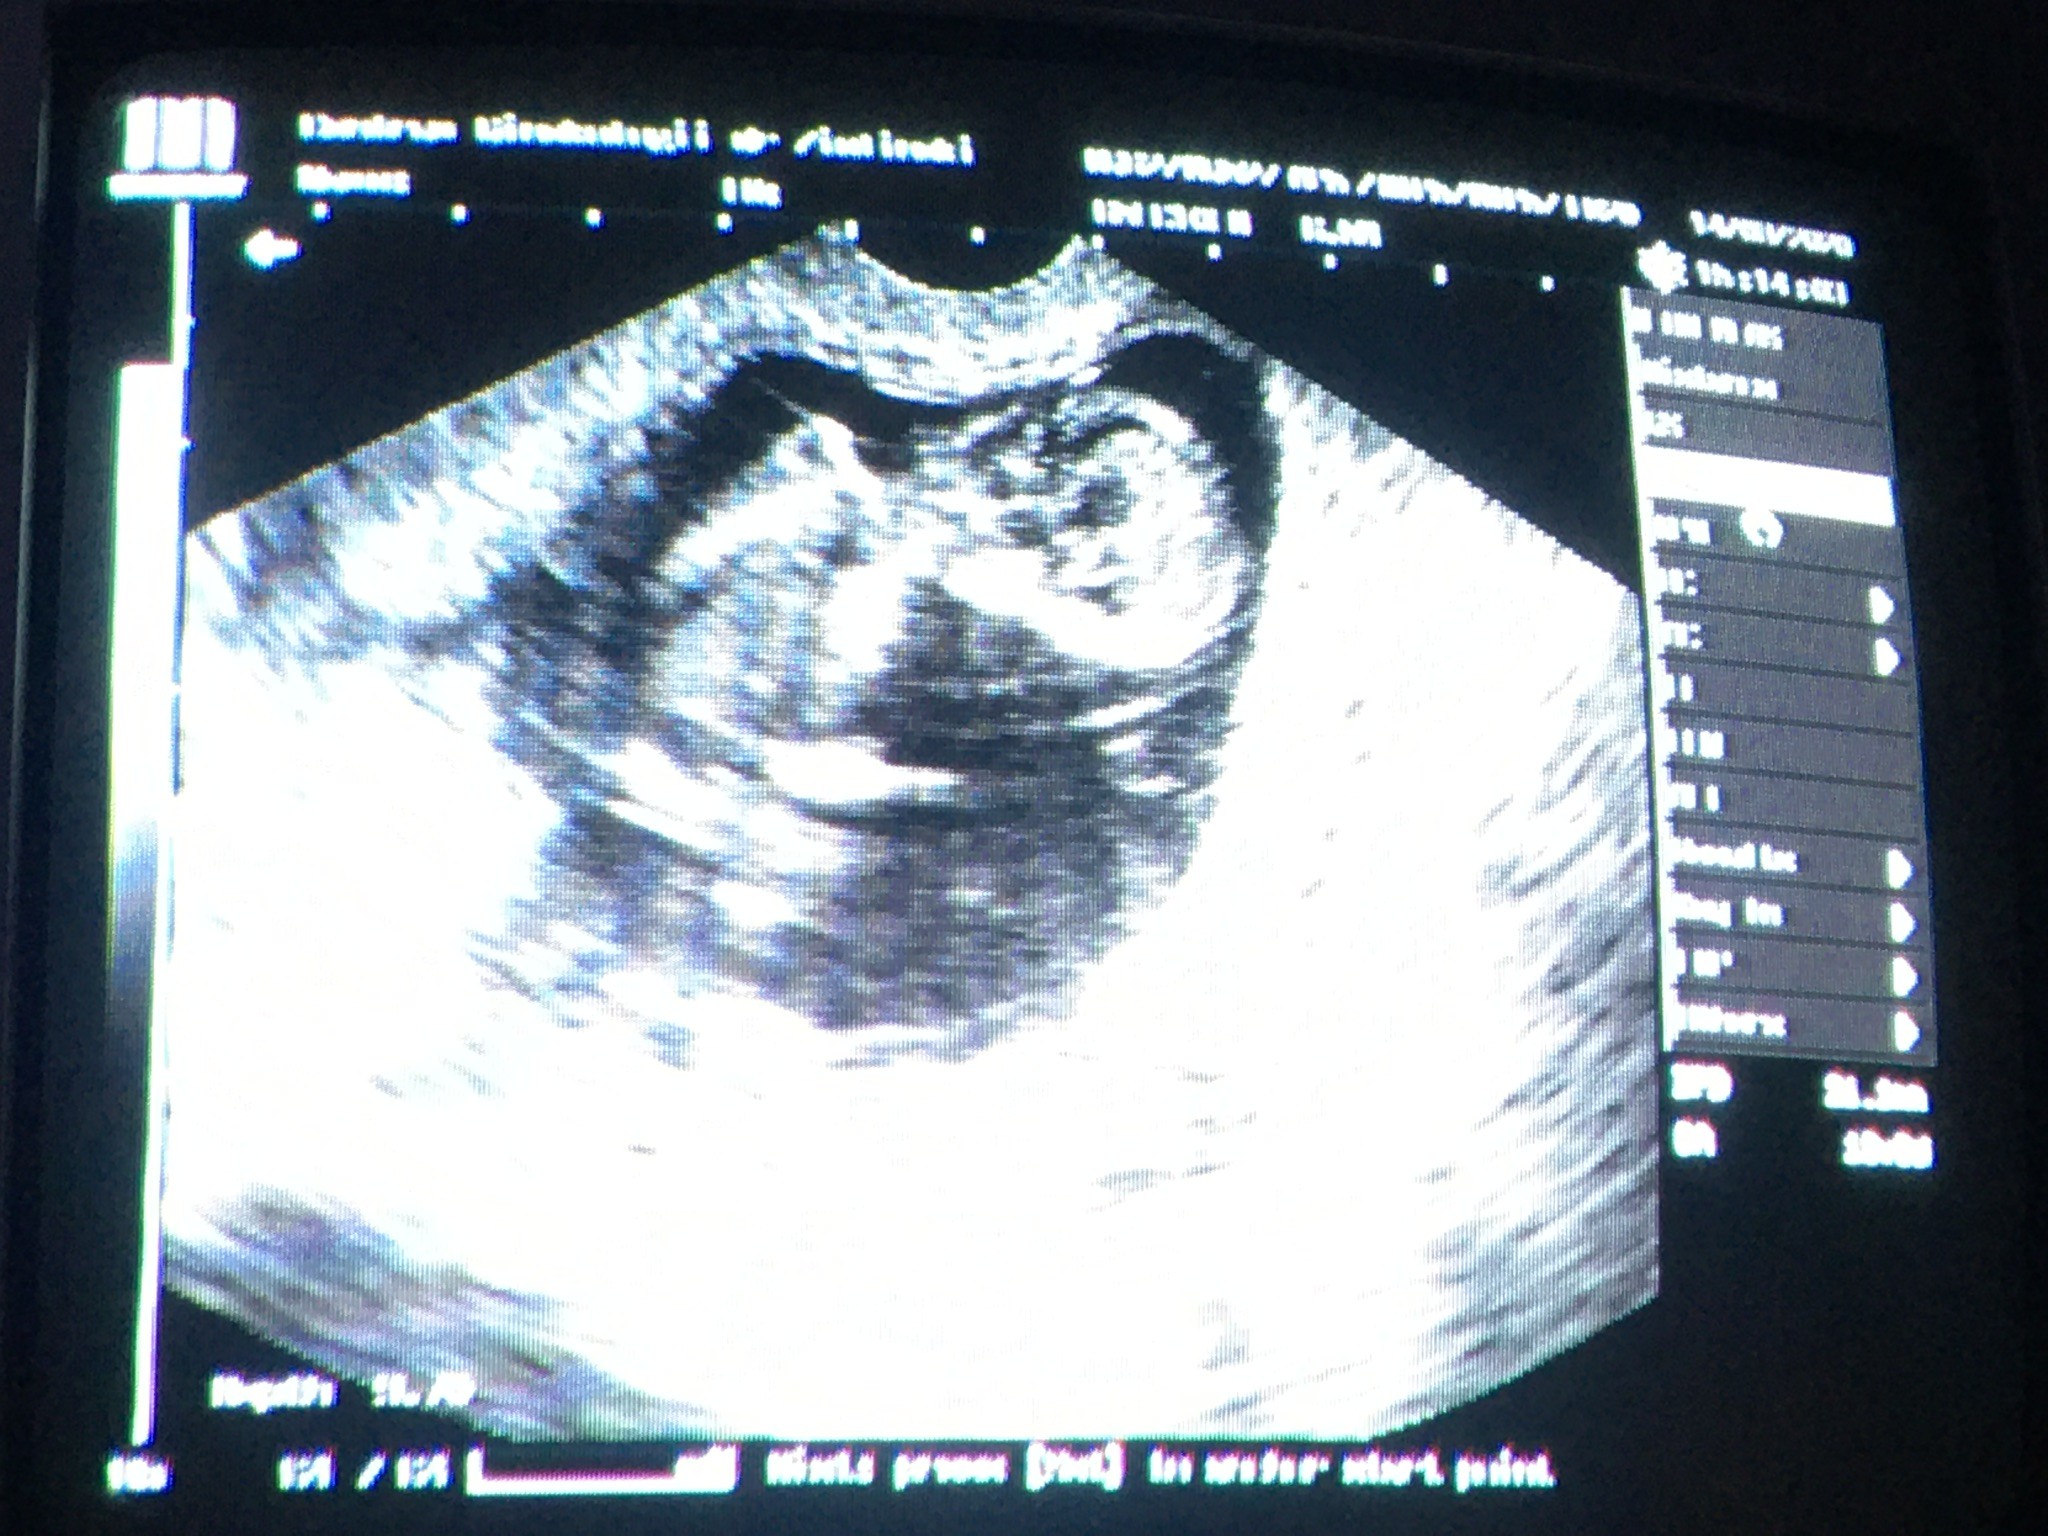

Hej kobietki miałam dac znać po kolejnej wizycie. Torbiel zmniejszyła się o 1cm ale obok pojawiła się cysta mała jeszcze ale póki co nic się nie dzieje wiec czekamy może moje hormony dadzą same radę. Z dzidzia wszystko okej rośnie zdrowo bardzo ruchliwa/y jest na usg. Ogólnie mój stan pomału lepiej dalej zmęczenie ale już mniej. Bóle głowy wieczorami. Wymiotuje tylko rano jak wstanę potem jak jem normalnie to bardzo rzadko. Mdłości tez już mniejsze. Wiec czekamy na kolejna wizytę 11 września i już liczę na płeć :)

Hej kobietki miałam dac znać po kolejnej wizycie. Torbiel zmniejszyła się o 1cm ale obok pojawiła się cysta mała jeszcze ale póki co nic się nie dzieje wiec czekamy może moje hormony dadzą same radę. Z dzidzia wszystko okej rośnie zdrowo bardzo ruchliwa/y jest na usg. Ogólnie mój stan pomału lepiej dalej zmęczenie ale już mniej. Bóle głowy wieczorami. Wymiotuje tylko rano jak wstanę potem jak jem normalnie to bardzo rzadko. Mdłości tez już mniejsze. Wiec czekamy na kolejna wizytę 11 września i już liczę na płeć :) Zobacz załącznik 1164521